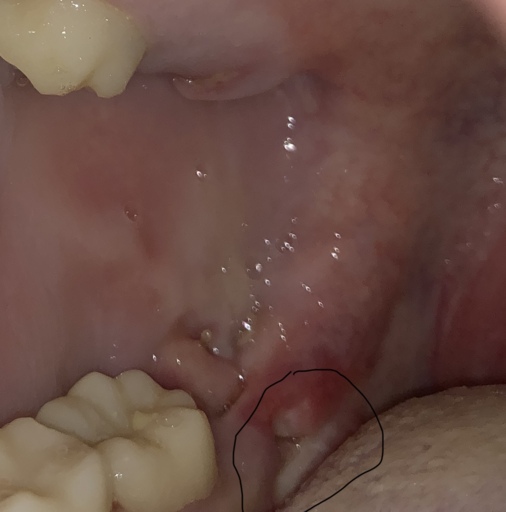

What shall i do with case complain from bone loss and gummy smile ?

case 26 old come to my clinic complain from her smile , after diagnosis is completed Patient suffer from gingival recession with bone loss in upper and lower arch , gingival dept in limited area was 4 , patient had bad history of orthodontic treatment with extraction of 2 upper canines and malaligment of teeth , she complain from pulmonary problems and mouth breather with v shape arch What shall i do in this case